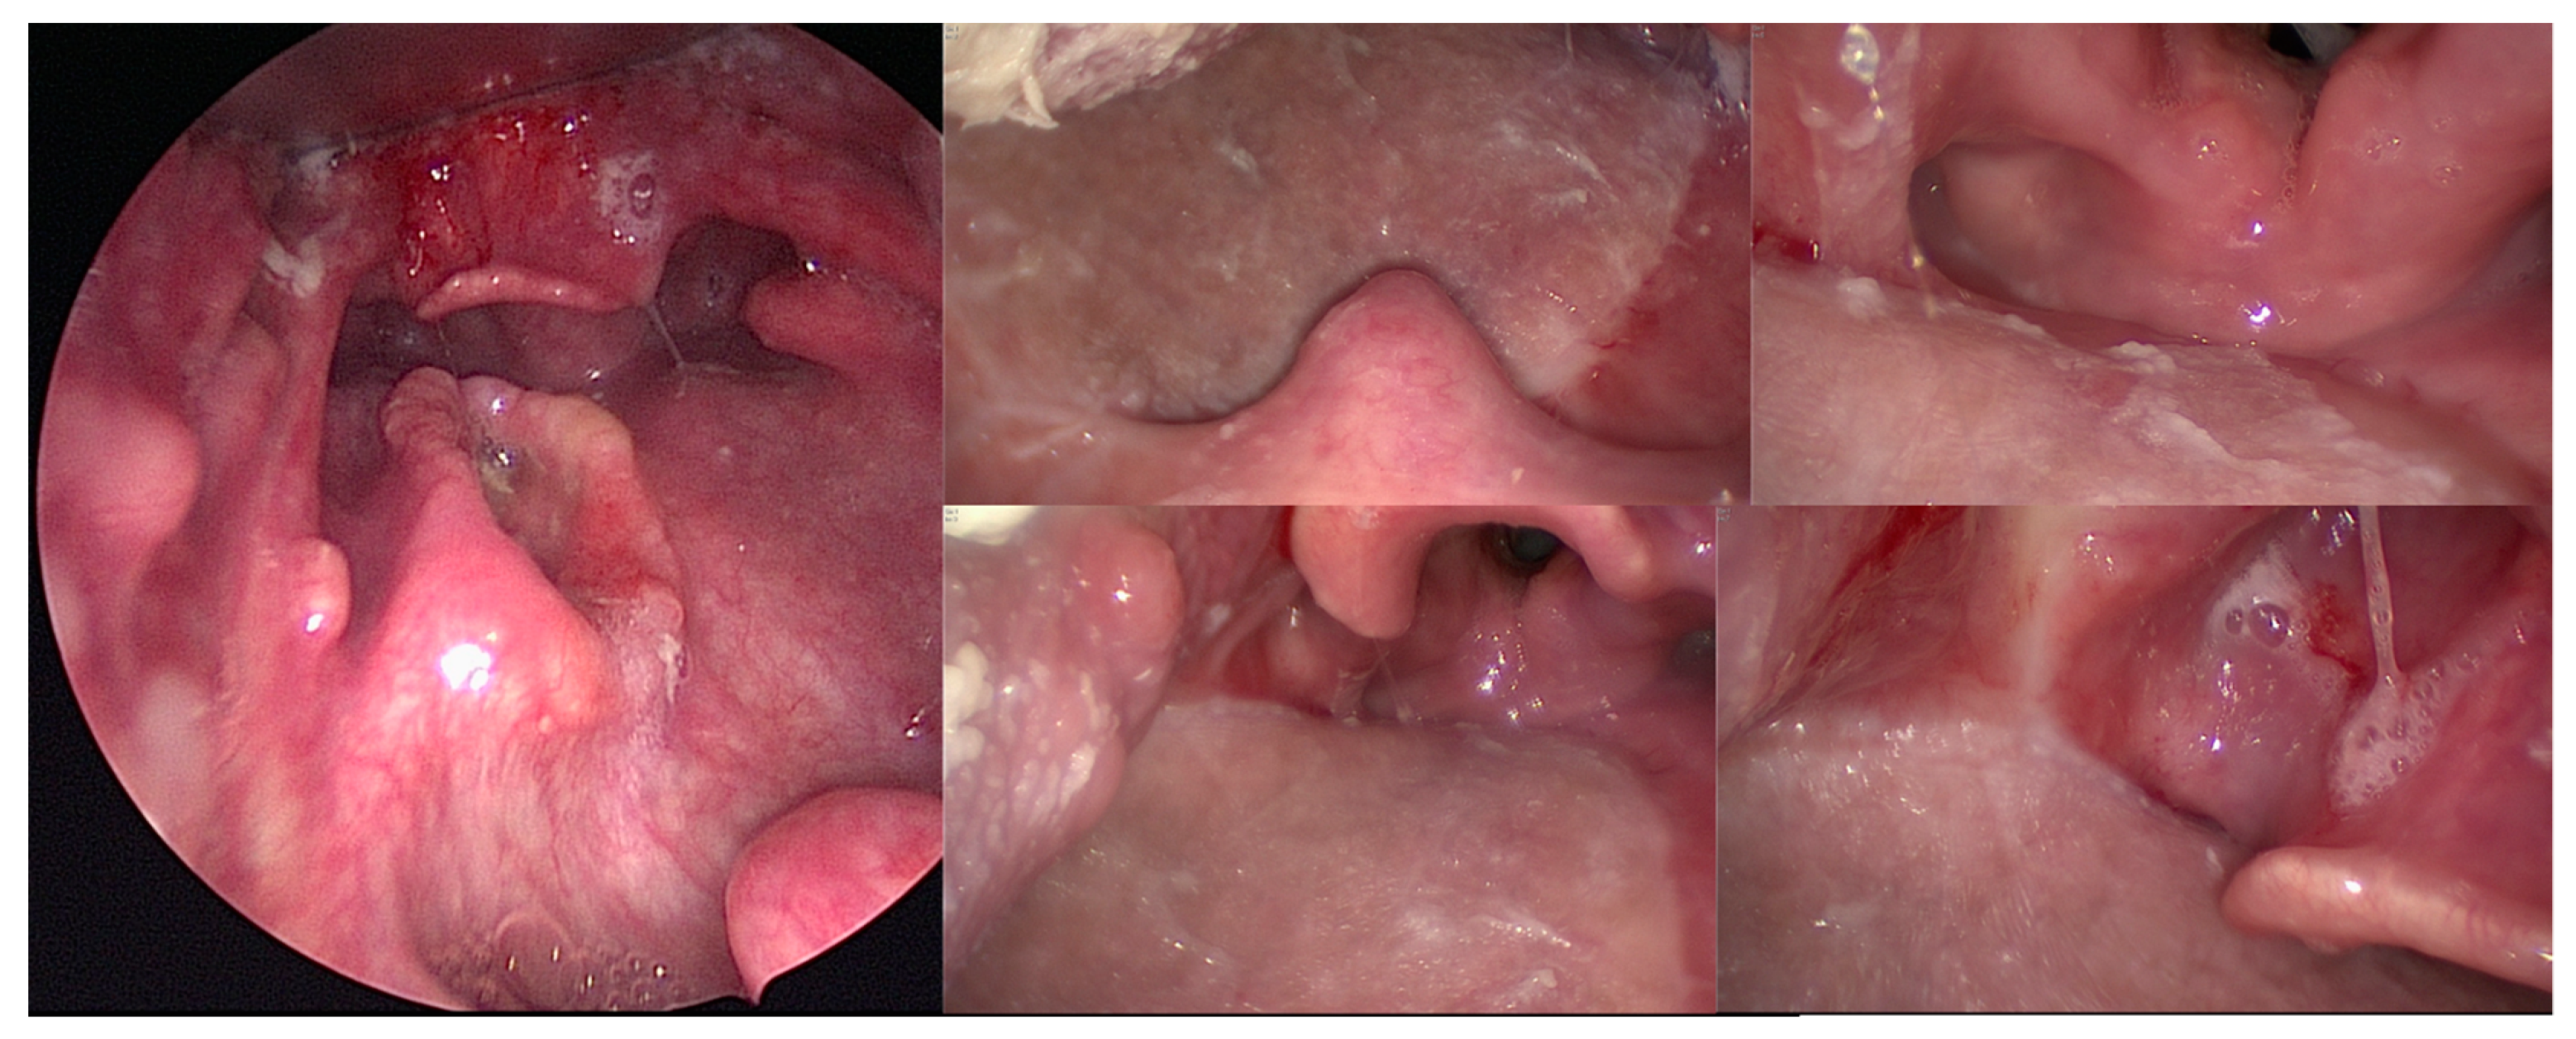

3.2. Peroperative Feasibility